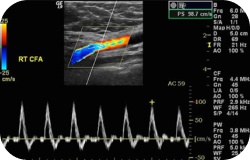

A pulse-doppler morphologic evaluation is used to evaluate blood flow through the major arteries of both lower extremities. This test is used to determine the velocity of blood flow within the arteries of both legs and find out the presence, amount, and location of arterial plaque.